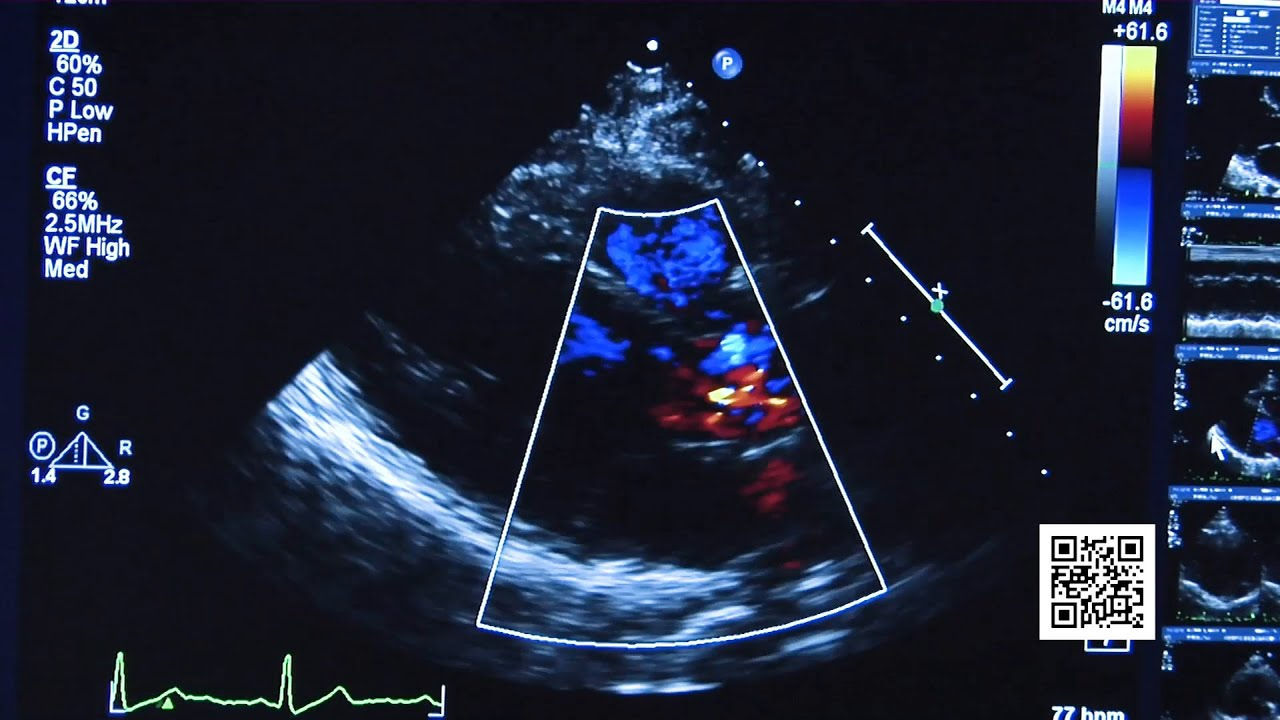

Atrial fibrillation is an irregular heartbeat caused by what physicians liken to a problem with the electrical wiring of the heart. Dr. George Dimeling talks about treating this condition.

Medications can be the first line of treatment that stabilize the heart rhythm. Interventional procedures, where a wire is brought in through a blood vessel can treat certain areas of the heart. And then level three would be an open surgical procedure where we find the conduction problems and isolate them from the heart so that they can't cause confusion in the wiring system any longer.